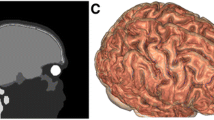

Figure 1a illustrates our TMS coil design (see reference [12] for details). In this study, the coil dimensions have been extended for human brain stimulation. For each single circular coil, the inner and outer diameters are 8 cm and 9 cm, respectively. The thickness of each single coil is 1 cm and 5 circular coils are accumulated along the central axis in this model. Considering the overall inductance of the coil model, we further extended the coil length while using narrow (lower value of ‘do–di’) but thick (higher value of h) coil windings, so that the total turn number could be low enough to control the coil inductance.

The head model is a homogenous sphere with the diameter of 17 cm and isotropic electrical conductivity of 0.33 S/m−1, The definitions of stimulation depth and focality in Fig. 1b are based on the half-value depth (d1/2) and half-value volume (V1/2). Modeling frequency was 5 kHz All conditions are identical to the modeling in the study by Deng et al. [5], except that the software we used for calculation is the COMSOL AC/DC module (finite element analysis software, COMSOL Inc.), which is different from that in their study. To calibrate our calculation using COMSOL, we firstly selected 4 coils, which were already documented in the study by Deng et al., and compared our results with theirs. The selected coil models for calculation calibration were the 50 mm, 70 mm and 90 mm circular and the 70 mm figure-8 Magstim coils.